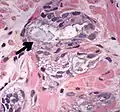

Intraductal carcinoma of the prostate with very patchy basal cells identified by immunohistochemistry. At least some of the glands lacking basal cell immunoreactivity represent intraductal rather than invasive carcinoma (a haematoxylin and eosin, b CK 5/6)[19]